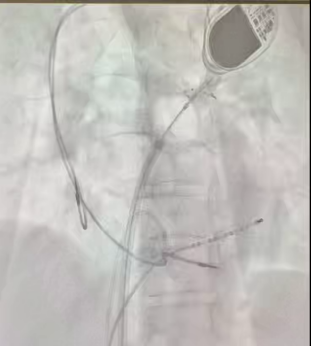

术前将DSA显示系统调整为180°镜像模式。术中,局部麻醉下建立股静脉通路,右侧置入2极和可调弯10极,左侧置入房间隔穿刺系统,通过造影剂确认房间隔穿刺成功,保留导丝置换冷冻球囊系统到左房,依次对左上、左下、右上、右下肺静脉进行冷冻消融,在冷冻至右上肺静脉过程中,转为窦性心律,四根肺静脉房颤相关电位脱落明确,起搏验证确定双侧肺静脉电位隔离,手术顺利完成。

四根肺静脉冷冻消融图